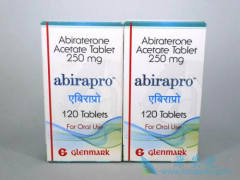

LATITUDE研究是一项双盲、安慰剂对照的Ⅲ期临床研究,纳入1199例高危mHSPC患者。其中mHSPC是指尚未接受过ADT或对ADT有疗效应答的转移性前列腺癌,而对于“高危”的定义,需要满足以下条件中的2~3条:①Gleason 评分≥8分;②3个以上的骨转移病灶;③可测 ...